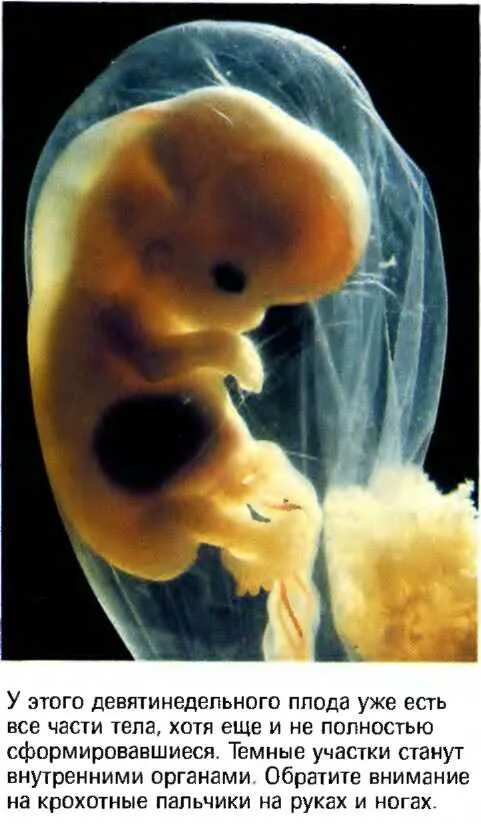

6 недель беременности как выглядит эмбрион